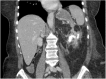

Xanthogranulomatous pyelonephritis (XGP) is a rare chronic granulomatous destructive process of the renal parenchyma. It is caused by a chronic inflammatory process due to recurrent urinary tract infections and/or obstructing renal calculi. Rarely, it presents with advanced complications including abscesses and fistula formations. In this article, we report a unique presentation of XGP with simultaneous upper and lower gastrointestinal bleeding in the setting of XGP with reno-gastric and reno-colic fistulas.